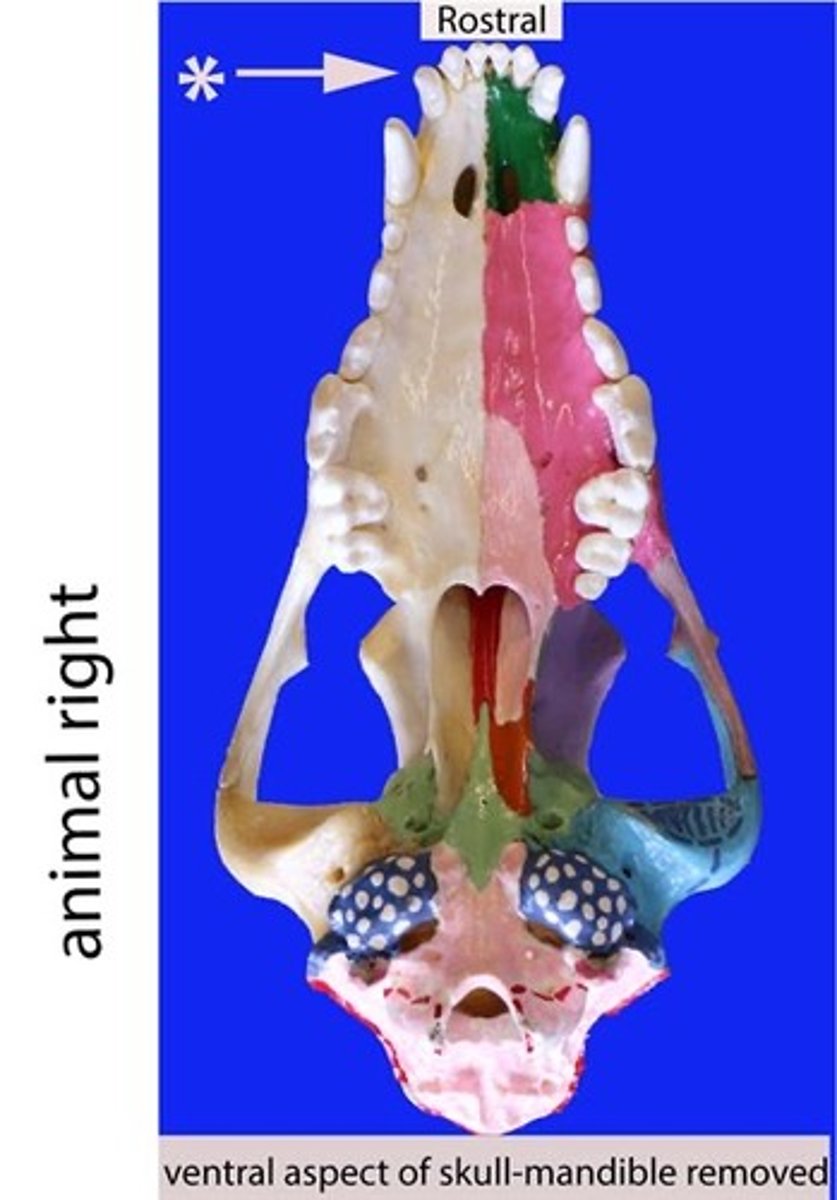

incisor

Identify the general type of tooth the arrow is pointing to

incisors

Identify the type of teeth shaded.